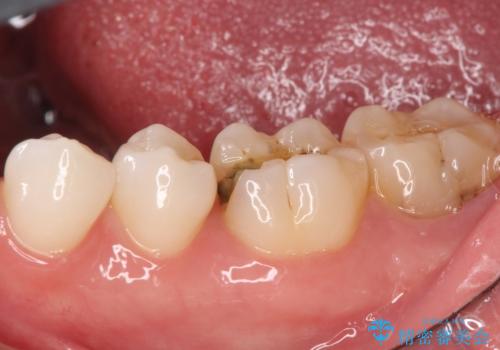

セラミックインレー 虫歯で欠けた歯の治療